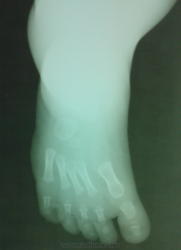

а, b Косолапость в возрасте 5 мес.: а) Рентгенограмма стопы в дорсальной проекции демонстрирует укорочение ахиллова сухожилия, отсутствие наклона пяточной кости от задненижнего до верхнепереднего положения и горизонтальное поражение таранной кости, вызывающее уменьшение таранно-пяточного угла;

b) Рентгенологическое исследование стопы в боковой проекции. Состояние приведения стопы (ось таранной кости латеральнее первой плюсневой кости) и уменьшение таранно-пяточного угла